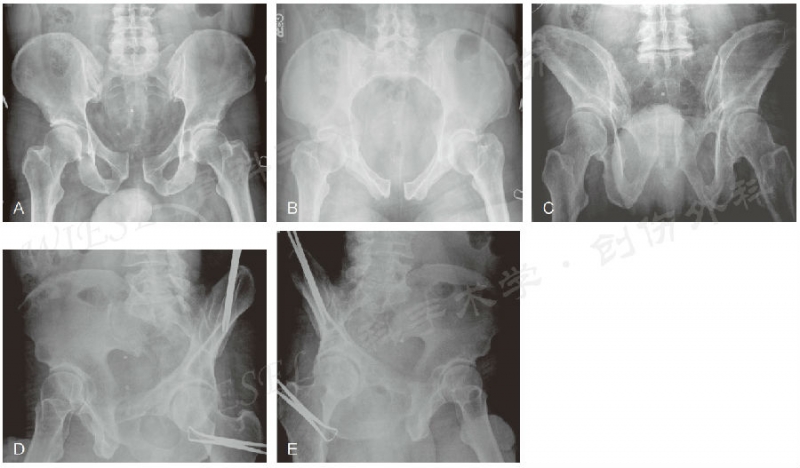

骨盆放射学检查包括前后位、入口位、出口位和Judet位(图5)。

图5 A~E.一例骨盆创伤、耻骨联合增宽患者的骨盆前后位(A)、入口位(B)、出口位(C) 以及Judet位(D、E)影像(经允许引自Jodi Siegel,MD&David Templeman,MD)